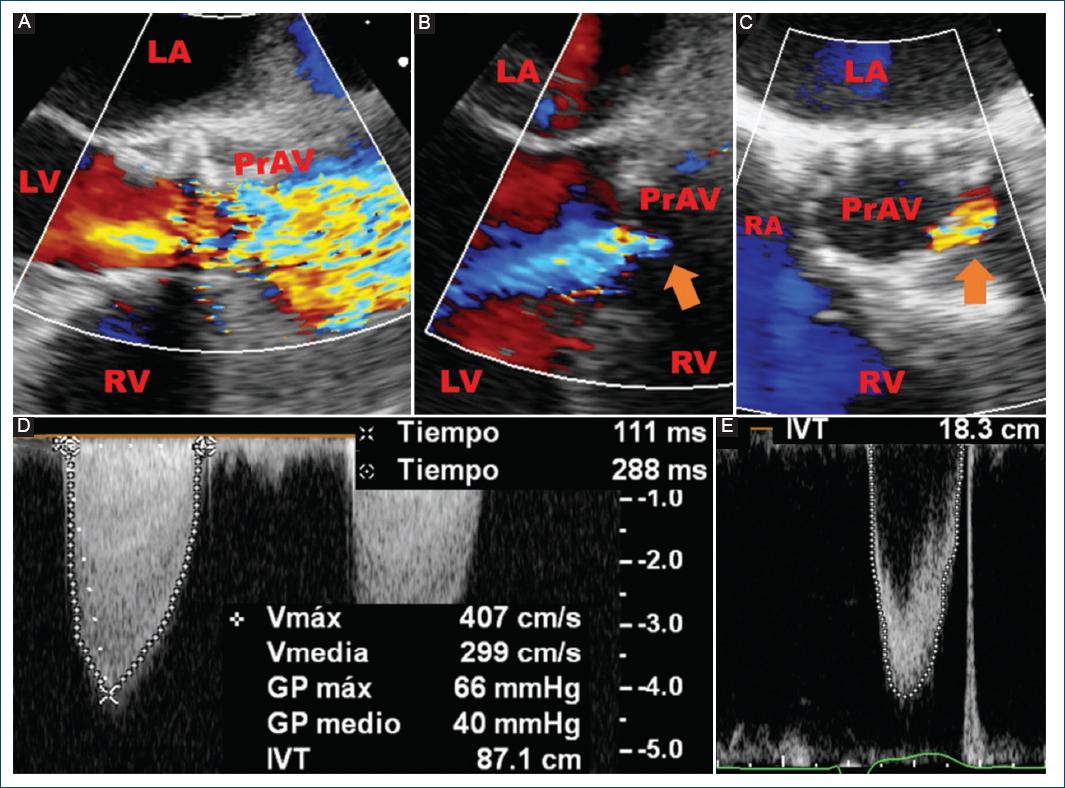

Figure 1 Transesophageal echocardiography: Prosthetic aortic valve with thickened transcatheter aortic valve replacement leaflets with abnormal mobility, valvular stenosis, and new occurrence of moderate regurgitation (orange arrow). Parameters: AT 111 ms, LVET 288 ms. AT/LVET ratio 0.38, peak velocity 4.07 m/s, peak gradient 66 mmHg, mean gradient 40 mmHg, VTILVOT 18.3 cm, VTIPrAV 87.1 cm, DVI 0.2 (baseline 0.58), EOA 0.6 cm2 (baseline 1.32 cm2). A: 2D image with color Doppler, mid-esophageal view at 135° (long axis). B: 2D image with color Doppler, mid-esophageal view at 135° (long axis). C: 2D image with color Doppler, mid-esophageal view at 45°. D: continuous-wave Doppler across prosthetic aortic valve. E: pulse-wave Doppler in the left ventricle outflow tract. AT: acceleration time;EOA: effective orifice area; DVI: Doppler velocity index; LA: left atrium;LV: left ventricle;LVET: left ventricular ejection time;RA: right atrium; RV: right ventricle; PrAV: prosthetic aortic valve; VTILVOT: left ventricular outflow tract velocity-time integral; VTIPrAV: prosthetic aortic valve velocity-time integral.